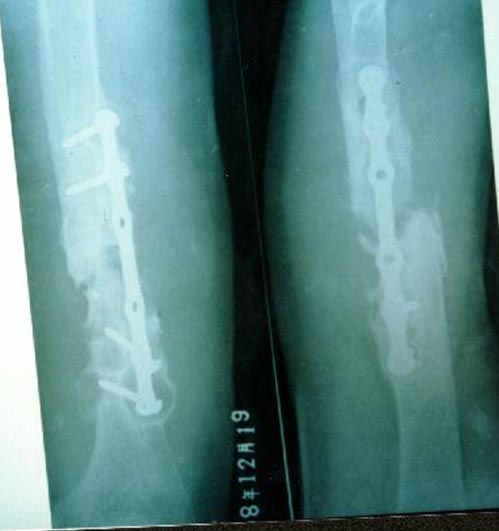

病例一、患者男性,60岁,肱骨远段开放粉碎骨折3年,骨不连,假关节形成。

图1-1我们用钢板固定骨折端提供支撑力,患者自体骨髓细胞经与异体骨和骨生长因子复合,

使没有细胞的植骨材料变成了有细胞的活骨。

图1-2 骨折在12个月后愈合,功能恢复满意。